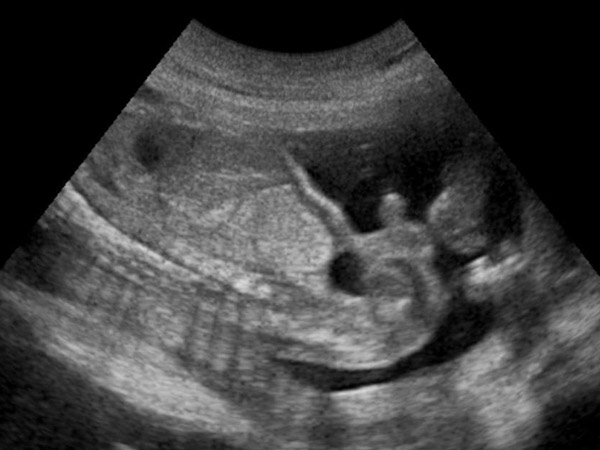

ಹೊಟ್ಟೆನೋವಿಗೆ ಕಾರಣ ಕಂಡುಕೊಂಡ ವೈದ್ಯರಿಗೆ ಆಘಾತ ಕಾದಿತ್ತು. ಗರ್ಭದಲ್ಲಿನ ಮಗು ಒದ್ದ ರಭಸ ಹೆಚ್ಚಾಗಿದ್ದು ಇದು ಗರ್ಭಾಶಯದ ಗೋಡೆಯನ್ನೇ ಸೀಳಿತ್ತು. ಮಗುವಿನ ಕಾಲು ಗರ್ಭಾಶಯದಿಂದ ಹೊರಚಾಚಿದ್ದು ಇದನ್ನು ಕಂಡ ವೈದ್ಯರಿಗೆ ತಮ್ಮ ಜೀವಮಾನದಲ್ಲಿಯೇ ಎಂದೂ ಕಾಣದ, ಕೇಳದ ವಿದ್ಯಮಾನ ಸಾಕ್ಷಾತ್ಕಾರವಾಗಿತ್ತು.

ಗರ್ಭಾಶಯದ ಘಾಸಿಯನ್ನು ಅವಲೋಕಿಸಿದ ವೈದ್ಯರು ಗರ್ಭಾಶಯದ ಗೋಡೆಯಲ್ಲಿ ಸುಮಾರು ಏಳು ಸೆಂಟಿಮೀಟರ್ ನಷ್ಟು ಉದ್ದದ ಗಾಯದ ಗುರುತು ಕಂಡು ಬಂದಿತ್ತು. ಈ ಗಾಯ ಗರ್ಭಾಶಯದ ಕೆಳಭಾಗದಲ್ಲಿದ್ದು ಈಕೆ ಗರ್ಭ ಧರಿಸುವ ಸುಮಾರು ಆರು ತಿಂಗಳ ಮುಂಚೆ ಶಸ್ತ್ರಕ್ರಿಯೆಗೆ ಒಳಗಾಗಿದ್ದ ಗುರುತಾಗಿತ್ತು. ಈ ಗಾಯ ಇತರ ಭಾಗದಷ್ಟು ದೃಢವಾಗಿಲ್ಲದೇ ಇದ್ದ ಕಾರಣ ಮಗುವಿನ ಒದೆತದಿಂದ ಸುಲಭವಾಗಿ ಮತ್ತೊಮ್ಮೆ ಬಿಚ್ಚಿಕೊಳ್ಳಲು ಸಾಧ್ಯವಾಗಿತ್ತು. ಅಕಸ್ಮಾತ್ತಾಗಿ ಸಂಭವಿಸಿದ ಈ ಘಟನೆಯಿಂದ ಗಾಯ ಮತ್ತೊಮ್ಮೆ ಬಿಚ್ಚಿಕೊಂಡು ಮಗುವಿನ ಕಾಲು ಹೊರಚಾಚುವಂತಾಗಿತ್ತು.

ಕಾರಣವೇನೇ ಇರಲಿ, ಈ ಘಟನೆ ಅತ್ಯಂತ ಅಪಾಯಕಾರಿಯಾಗಿದ್ದು ತಕ್ಷಣವೇ ಶಸ್ತ್ರಚಿಕಿತ್ಸೆಯ ಮೂಲಕ ಗರ್ಭಾಶಯವನ್ನು ಹೊಲಿದು ಸರಿಪಡಿಸುವುದು ಅನಿವಾರ್ಯವಾಗಿತ್ತು. ಅತ್ಯಂತ ಸೂಕ್ಷ್ಮವಾದ ಈ ಶಸ್ತ್ರಕ್ರಿಯೆ ಹಲವು ತಜ್ಞ ಶಸ್ತ್ರವೈದ್ಯರ ನೆರವಿನಿಂದ ಸುಮಾರು ಹತ್ತು ಘಂಟೆಗಳ ಕಾಲ ನಡೆದು ಕಡೆಗೂ ಶಸ್ತ್ರಚಿಕಿತ್ಸೆ ಯಶಸ್ವಿಯಾಗಿತ್ತು. ಬಳಿಕ ತಾಯಿ ಹಾಗೂ ಮಗು ಸುರಕ್ಷಿತರಾಗಿದ್ದಾರೆ ಎಂದು ವೈದ್ಯರು ಘೋಷಿಸಿದ ಬಳಿಕ ಎಲ್ಲರೂ ನಿಟ್ಟುಸಿರು ಬಿಟ್ಟರು. ಶಸ್ತ್ರಕ್ರಿಯೆ ಇಷ್ಟು ಜಟಿಲವಾಗಲು ಕಾರಣವೇನೆಂದರೆ ಗರ್ಭಾಶಯದೊಳಗೆ ಮಗುವನ್ನು ಆವರಿಸಿರುವ ಆಮ್ನಿಯಾಟಿಕ್ ದ್ರವ ಗರ್ಭಕೋಶದ ಗೋಡೆ ಸೀಳಿದ್ದರಿಂದ ಹೊರಚೆಲ್ಲಿ ಗರ್ಭಿಣಿಯ ರಕ್ತದೊಡನೆ ಬೆರೆತಿತ್ತು.